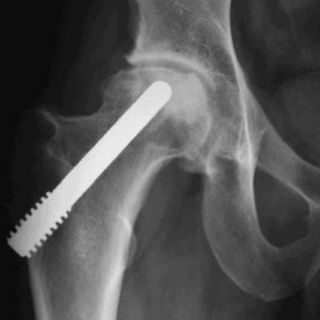

Los especialistas del Instituto Nacional de Rehabilitación, Genaro Rico, Javier Linares y Roberto González, mostraron una línea mexicana de prótesis para reconstrucción fémur, rodilla, húmero, cadera y en general huesos de brazos y piernas con cáncer óseo.

Refirió que en 1990 se iniciaron las cirugías para colocar prótesis del país, pues las importadas utilizan un cemento que ocasiona alteraciones de la mecánica del hueso, además de que no siempre servían porque eran muy grandes para la talla de pacientes mexicanos.

Otros de los beneficios de estas prótesis de manufactura mexicana son que tienen un costo mucho menor, pues las adquiridas del extranjero, por ejemplo la de rodilla, puede tener un valor de hasta 400 mil pesos, expuso.

En tanto, el doctor Genaro Linares, dijo que las prótesis mexicanas están patentadas y son fabricadas en Puebla, y a la fecha han sido colocadas casi 300, muchas de ellas a pacientes de escasos recursos, que son apoyados por fundaciones e instituciones.